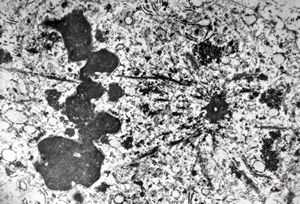

F, 1m. | sepsis - mycotic dermal lesions

M, 57y. | dermal mycotic lesion

M, 57y. | dermal mycotic lesion … toluidine-blue stained semithin section